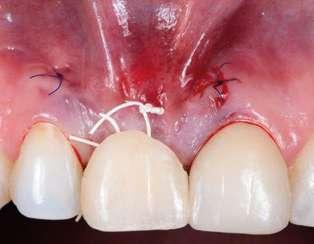

na paciente de 35 años (Figura 1) fue remitida a la Clínica de Odontología Reconstructiva de la Universidad de Zúrich debido a una infección crónica en el diente 11 y con expectativas estéticas muy altas. El diente 11 había sufrido un trauma hace 10 años y había sido tratado con multiple endodoncias sin éxito. El diente presentaba un absceso bucal (Figura 2), una bolsa periodontal aislado de 9 mm, y una ausencia de la tabla vestibular ósea (Figura 3). El diagnóstico se estableció como una fractura radicular vertical, lo que resultó en un pronóstico pobre. El plan de tratamiento consistió en una extracción combinada con preservación alveolar, colocación de implante diferido con injerto de tejido conectivo, una corona cerámica implantosoportada en 11 y una nueva carilla de cerámica para el diente 21.

El diente 11 fue extraído (Figura 4), seguido por la preservación alveolar. Se realizó un injerto pediculado de espesor parcial rotado del paladar (Figura 5), junto con una membrana de colágeno reabsorbible, un xeno-injerto bovino y cianoacrilato sellando al alveolo (Figura 6). La provisionalización consistió en un puente adhesivo de resina con dos alas de metal. El alveolo se dejó cicatrizar durante 6 meses, después de los cuales se tomó una impresión digital así como un escáner CBCT (Figura 7). Se llevó

a cabo una planificación digital para una cirugía guiada de implante en una posición protéticamente ideal (Figura 8). El implante 11 se colocó completamente guiado a través de una férula (Figura 9). Las dimensiones del reborde alveolar eran ideales para la colocación del implante en una posición atornillada (Figura 10), al igual que la calidad del hueso cicatrizado. Un injerto de tejido conectivo subepitelial fue estabilizado ocluso-bucalmente al implante (Figura 11) y el puente adhesivo fue recementado (Figura 12). Después de 3 meses de cicatrización, se realizó una restauración provisional y se acondicionó adecuadamente para dar forma al perfil de emergencia, imitando el del diente adyacente (Figura 13). Después de una fase provisional, se tomó una impresión analógica individualizada para el implante 11 y el diente 21 (Figura 14). El laboratorio fabricó una corona implantosoportada de zirconio con cerámica estratificada para el 11 y una carilla laminada feldespática para el diente 21 (Figura 15). Ambas restauraciones fueron colocadas en la paciente y mantenidas. La paciente quedó muy satisfecha con el resultado estético de las restauraciones (Figuras 16, 17). Después de 2 años, el implante permanece saludable con el hueso marginal estable (Figura 18) y una buena calidad y cantidad de tejido blando.

Una correcta planificación digital fue clave para definir los objetivos del tratamiento y el manejo detallado de un caso complejo en una paciente con alta demanda estética. Realizar la preservación alveolar para mejorar las dimensiones volumétricas antes de la colocación del implante facilitó una implantación

guiada sin necesidad adicional de aumento de cresta. La planificación digital con cirugía guiada permitió la implantación en una posición atornillada ideal. La fase de provisionalización consiguió dotar al perfil de emergencia de una apariencia estética y natural. Las dos restauraciones cerámicas resultaron simétricas y muy estéticas para una paciente satisfecha. 